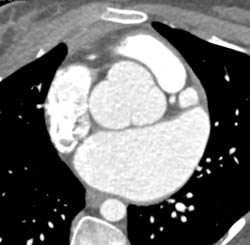

Extensive Plaque in LAD